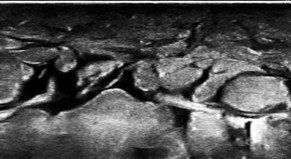

実は上記にあるような疾患によるむくみより、足のむくみを心臓に返すための筋ポンプの衰えが原因であることが最も多いです。超音波で診ると、足首の上の皮膚の下で、脂肪組織の間に組織液が溜まって敷石状に見えるほどむくんでいる方がたくさんいらっしゃいます。

(図3)